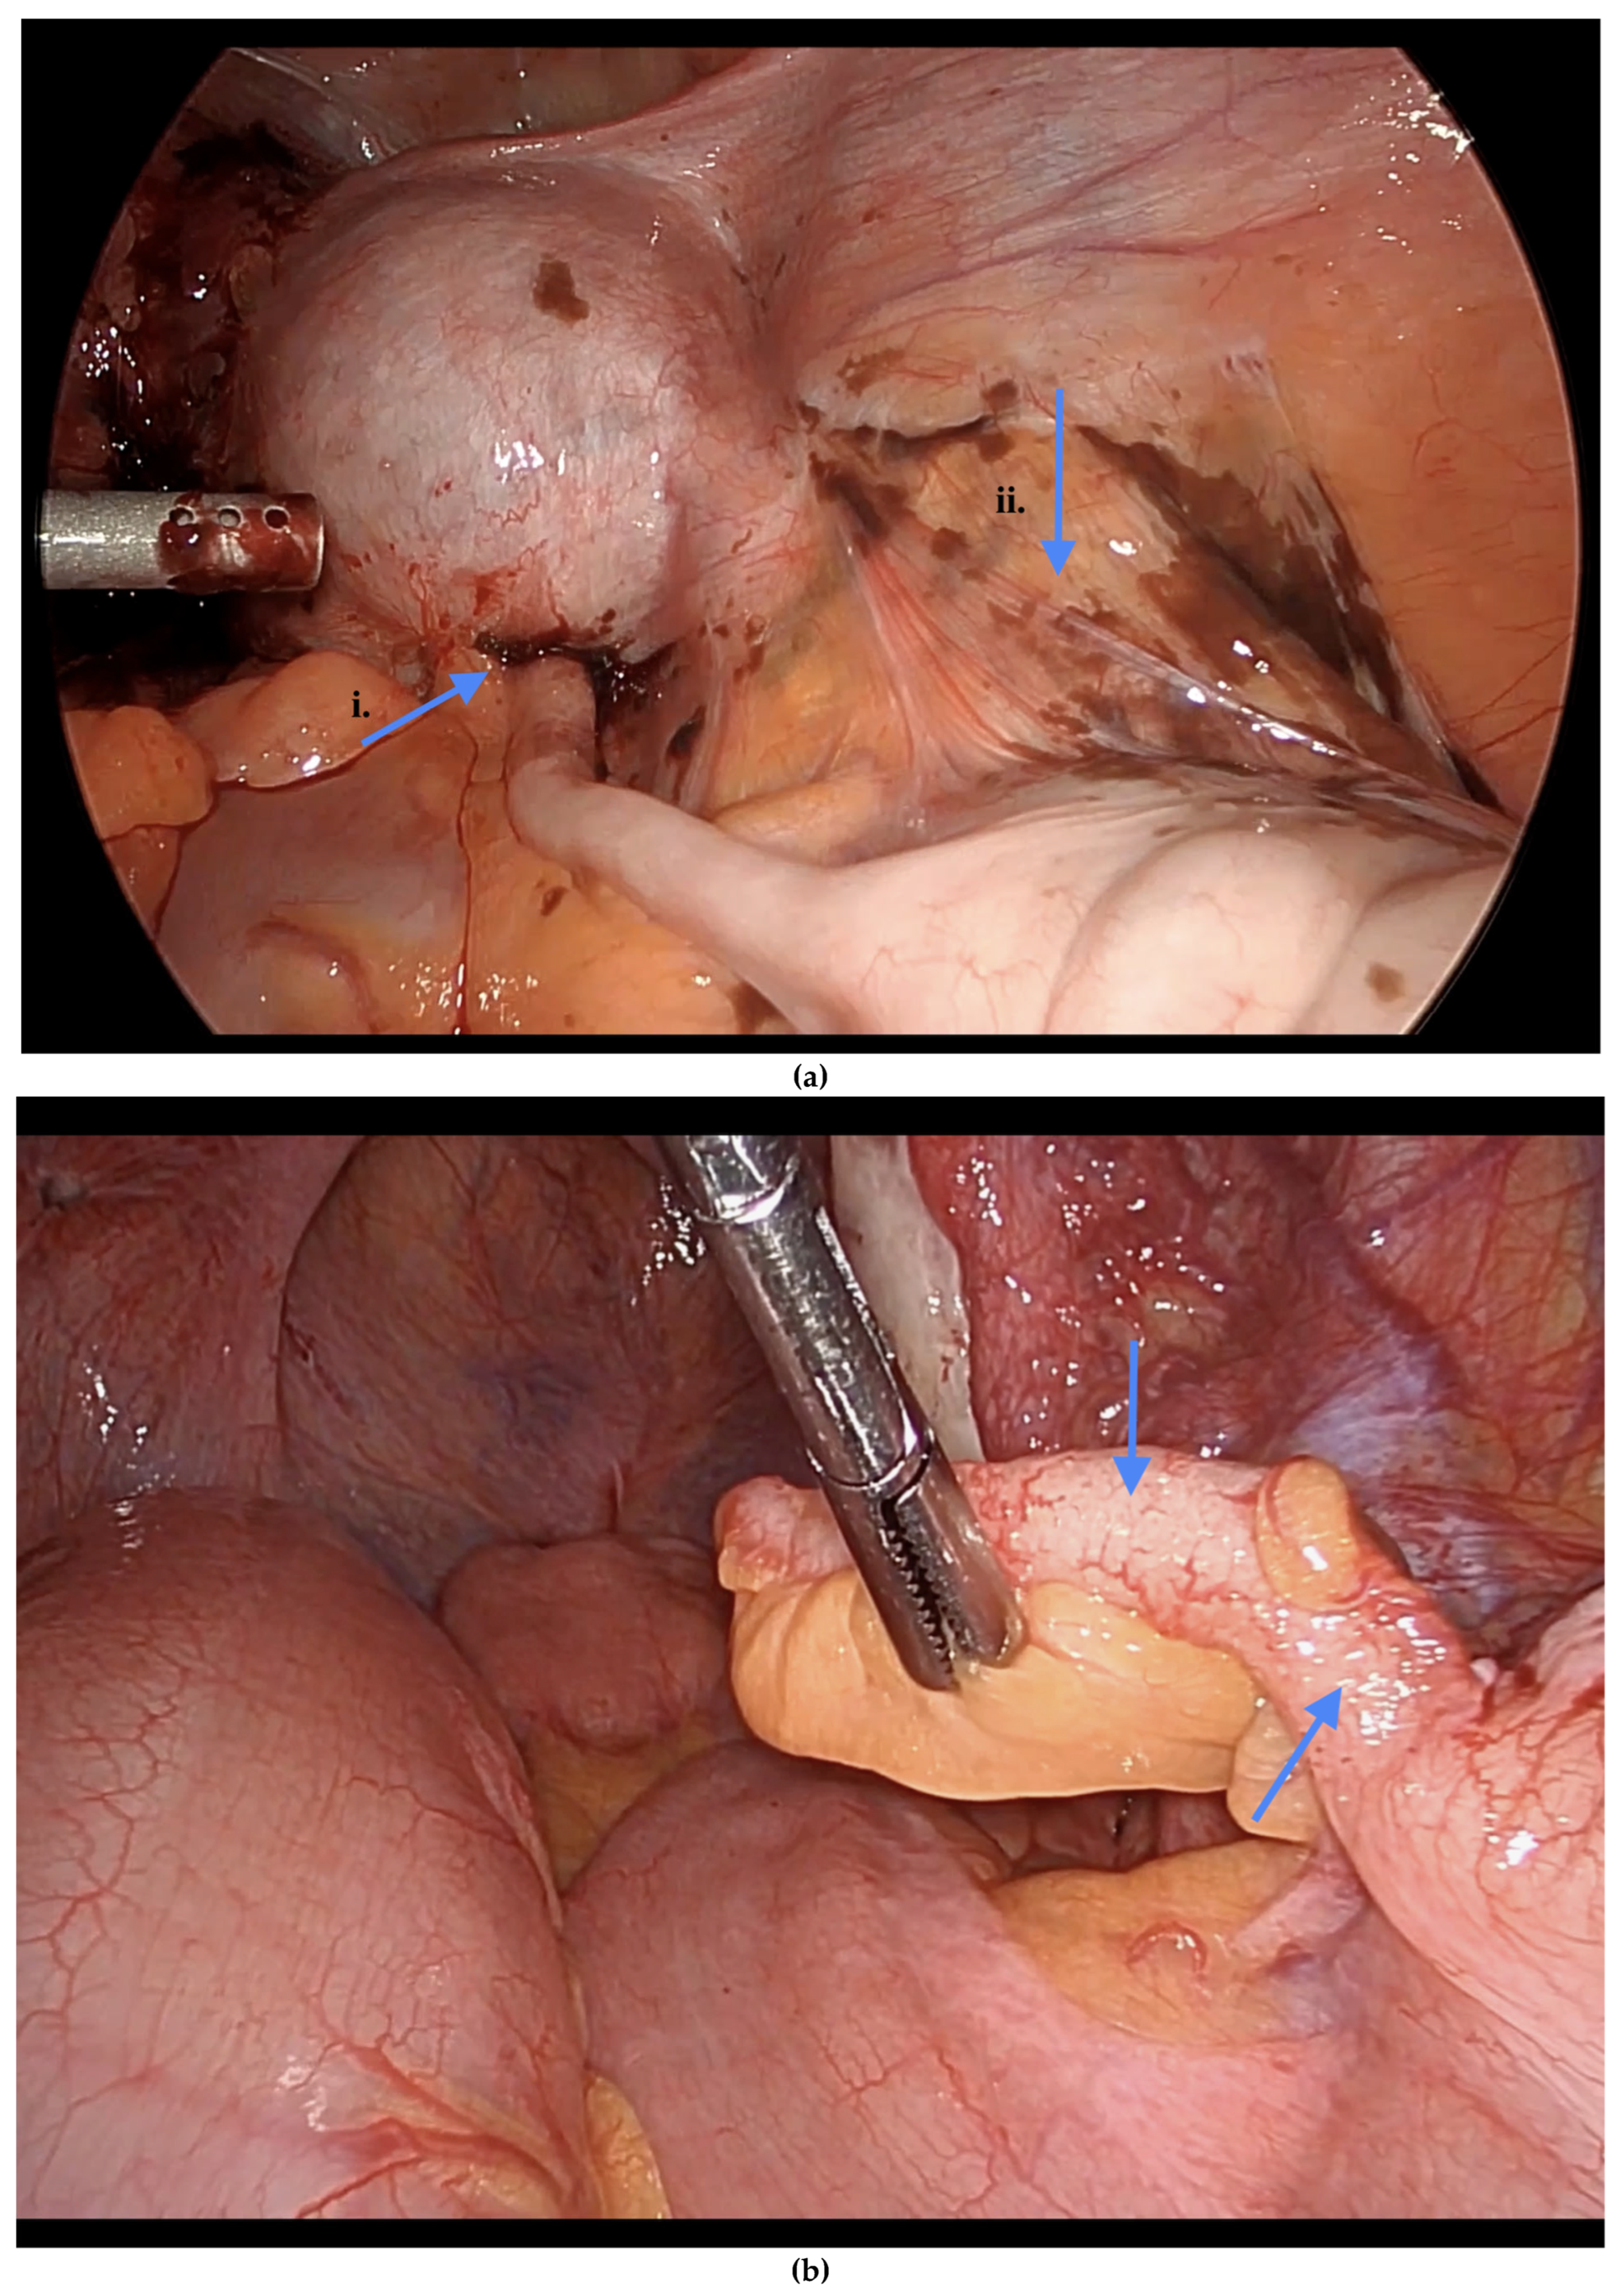

Informed consent was obtained preoperatively, which included a discussion of the possibility of intraoperative appendectomy if appendiceal abnormalities were identified. During surgery, after optimal excision and ablation of endometriotic lesions, the appendix was carefully evaluated for evidence of endometriotic implants, serosal abnormalities, adhesions, fibrous obliteration, or features suggestive of acute or chronic appendicitis (Figure 1, Figure 2 and Figure 3). If abnormal findings were present, intravenous metronidazole was administered for infection prophylaxis, and a laparoscopic appendectomy was performed using the existing port sites [15]. The surgical technique included division of the mesoappendix, followed by transection and closure of the appendiceal base using a vascular stapler. The specimen was placed into a laparoscopic retrieval pouch and sent for histopathologic analysis [15,16].

Among the 216 patients with confirmed appendiceal abnormalities, many presented with more than one pathological finding (Figure 1, Figure 2 and Figure 3). Specifically, 34 patients (14.41%) had histologically confirmed appendiceal endometriosis lesions, 140 patients (59.32%) showed focal or serosal adhesions, 82 (34.75%) demonstrated fibrous obliteration, typically observed as obliteration of the appendiceal tip, and 20 (8.47%) exhibited signs of inflammation. Notably, three cases were diagnosed with neuroendocrine tumors of the appendix: one was confirmed to be malignant, while the other two were benign (Table 2).

Figure 3. (a) i. Fibrous obliteration, and endometriosis at the tip. ii. Inflammation of the appendix indicating possible acute appendicitis. (b) Endometriosis on the tip of the appendix. Blue arrows indicate (a) (i) fibrous obliteration and endometriosis at the tip of the appendix, and (ii) inflammation suggesting possible acute appendicitis; and (b) endometriosis at the tip of the appendix.